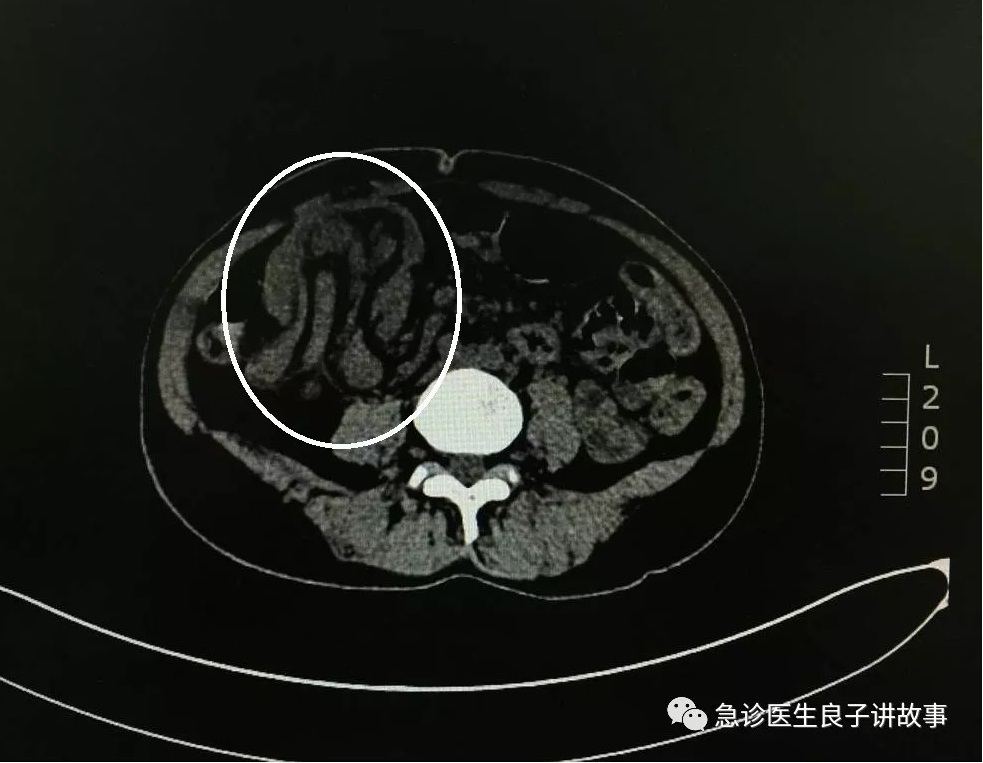

和家属好好的交流一下,也许哪里有问题,毕竟是淋巴瘤患者,要慎重加小心,建议做CT。不得不佩服我们的医院,24小时的CT检查,必要时还有强化CT可做。非常的迅速,CT片子就摆在我的面前了。看着CT的影像,太不可思议了,难道是一位成年“肠套叠”!这种病太少见了,资料上说,儿童尤其是2岁以内的婴幼儿“肠套叠”多见,成年人仅占肠套叠患者不到2%。还有问题吗??这位患者是否需要手术治疗呢?这就需要我们的外科医生来评价了,我终于找到患者的原因了,后背一阵阵的冷汗一直往下流。

后记:成人肠套叠的确非常少见,大部分表现不典型,好发于炎性肠病、meckel憩室和肿瘤患者,一般来说超声比较敏感,但是这对超声医师有相当高的要求,比较而言CT诊断的敏感性更高,而且又特异性的表现,比如同心圆征,套入征等。